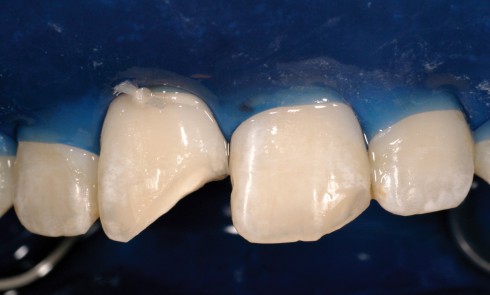

Article réservé à nos abonnés Restauration esthétique directe d’un angle incisif fracturé

Les restaurations antérieures en composite font partie de nos plans de traitement au quotidien. Cependant, leur apparente complexité et leur...